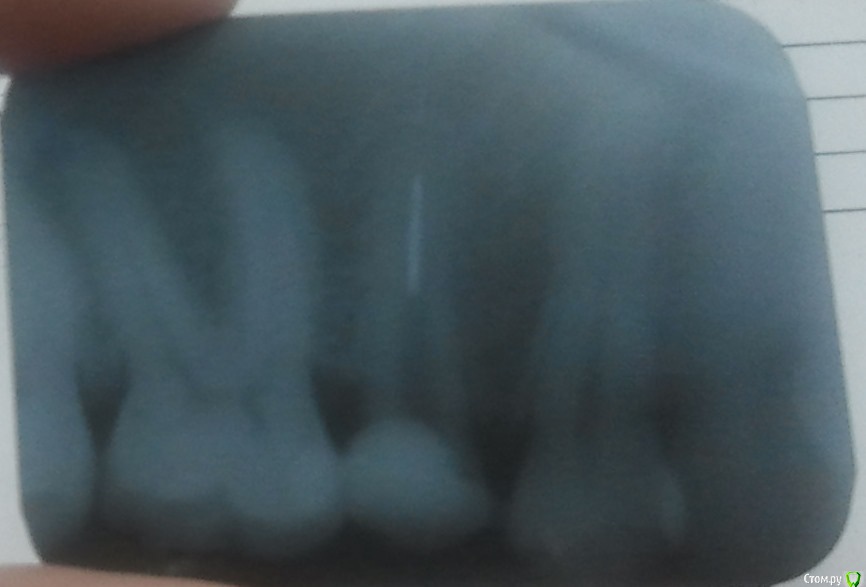

nastik2083 Опубликовано 9 октября, 2015 Поделиться Опубликовано 9 октября, 2015 Здравствуйте! Зуб нижний справа 5-й. лет 7 назад был депульпирован, поставлен серебряный штифт и пломба. Пломба пару раз выпадала, терапевты говорили о коронке, но говорили, что штифт не вытащить и ставили пломбу. В итоге кусочек зуба откололся, пошла к терапевту в специализированную клинику. После 40 минут работы освободили часть канала (около 8 мм из 16), в остальной части остался штифт, зуб сточили под уровень десны (скол был тоже вровень с десной с одной стороны). Вопрос у меня нормально ли что оставили кусок штифта в канале? Какую коронку ставить? у меня уже стоит имплант с цирконием и чувствует себя хорошо. Эстетика важна мне, но 5-й не особо видно. Я аллергик, например на желтое золото у меня сыпь, на белое нет. На часы вроде тоже нет, была аллергия на ремешок кожаный, но в области металла не было, только в месте где кожаный ремешок. Читала что цирконий более долговечен и для десен лучше. Все-таки с десной видимо будет соприкасаться. Снимок у меня только прицельный, сфоткала его как могла, видно конечно очень плохо. Цирконий или МК? Ссылка на комментарий

kozloff Опубликовано 9 октября, 2015 Поделиться Опубликовано 9 октября, 2015 Цирконий. Почему рассматриваете м/к? Решили немного сэкономить на своём здоровье? Вопросов больше к корневому каналу. Штифт извлекли не полностью? На данном снимке канал не запломбирован должным образом, коронку пока нельзя ставить. Ссылка на комментарий

red_butler Опубликовано 9 октября, 2015 Поделиться Опубликовано 9 октября, 2015 снимок бы в лучшем качестве посмотреть. Ссылка на комментарий